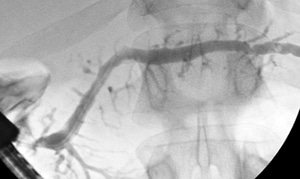

An endERCP is the most appropriate procedure to remove stones from the bile duct. On this X-ray, there are multiple stones lodged in the bile duct.